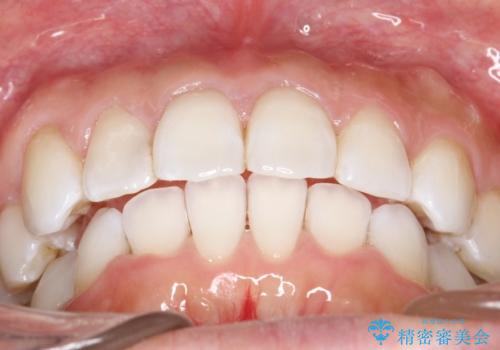

抜歯せずに八重歯のマウスピース矯正

- 非抜歯・遠心移動+IPR+拡大 によるマウスピース矯正を計画した。

八重歯がシビアな場合、抜歯をしないと治せないケースもありますが、奥歯の位置関係を修正したり、歯のサイズダウンを行うことで、抜歯をせずに改善できる場合もたくさんあります。